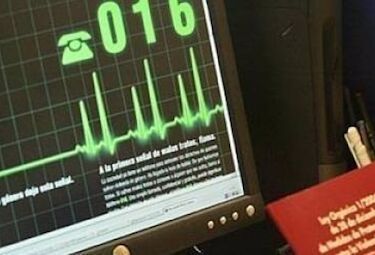

El SES cita a cerca de 8.000 mujeres para realizarse mamografías durante el mes de mayo

Unas 3.500 usuarias están citadas para realizarse la prueba en las dos unidades móviles con que cuenta el Programa de Detección Precoz de Cáncer de...